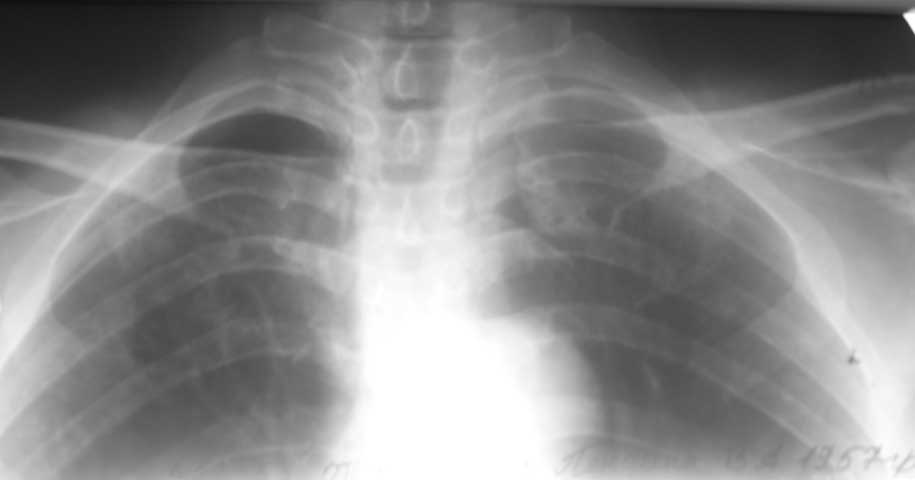

синдром Тице

Уважаемые коллеги! Подскажите, есть ли какие нибудь новые методы лечения болезни Тице?

В литературе указаны только физиопроцедуры, препараты кальция, новокаиновые блокады.